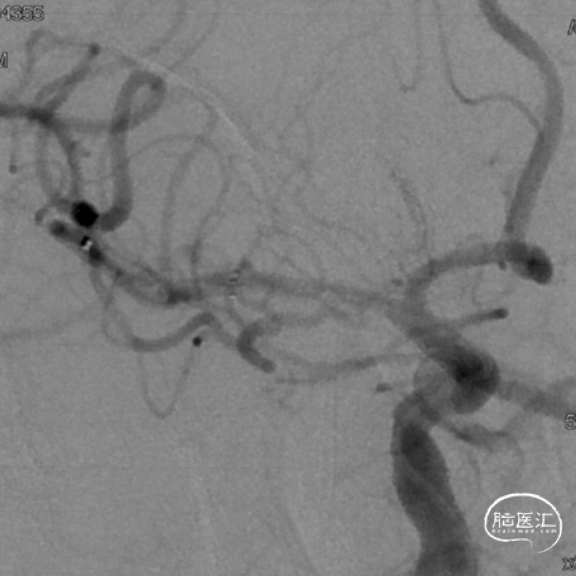

撤出导管导丝后造影,可见靶血管支架贴壁良好,前向血流通畅稳定。

术后行Dyna-CT未见异常,支架定位准确,贴壁良好。

再次造影观察,确认手术成功,结束手术。

复查脑血管造影示:右侧大脑中动脉支架置入术后,支架位置良好,管腔内血流通畅,未见明显狭窄。